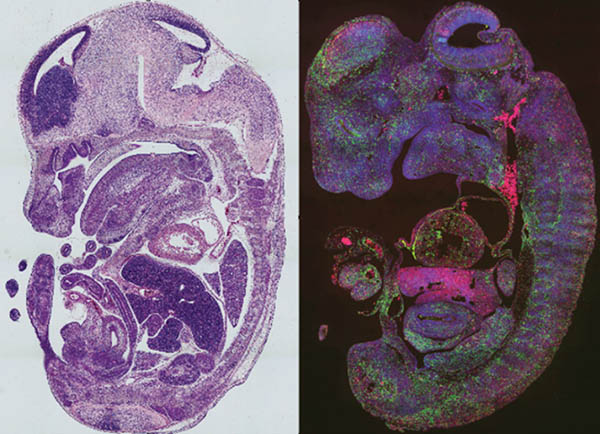

The lab takes advantage of multiple cutting-edge technologies, including single cell RNA sequencing, ribosome profiling, ChIP-sequencing, CROP-Seq, ATAC-Seq, special transcriptomics, proteomics, CRISPR-Cas9 and confocal imaging, and generates and uses genetic mouse models and human induced pluripotent cells to tackle these and other important questions in the field.

Congenital heart disease (CHD) is the most common birth defect, affecting nearly 1% of live births. By expanding knowledge of the pathogenesis of CHD, the lab team aims to improve CHD treatment and prevention and adult heart repair and regeneration.

A key process in heart development is ventricular trabeculation and compaction. The failure of this process can result in left ventricular noncompaction cardiomyopathy (LVNC), the third most common form of cardiomyopathy. The etiology of LVNC is still poorly understood, warranting further investigation.

During early heart development, the derivation and commitment of each cardiac lineage is crucial for later cardiac morphogenesis. However, in-depth understandings of lineage specification are still lacking.

Our lab is interested in learning how cardiac lineages are defined at epigenetic level. For instance, how chromatin accessibility may sculpture diversified cardiac lineages including subtypes of cardiomyocyte lineages.